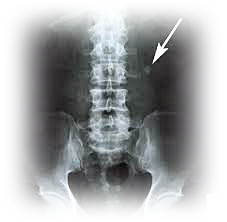

이러한 결석은 보통 신장에서 발생합니다.

신장, 요도, 방광, 요도 등에 있습니다